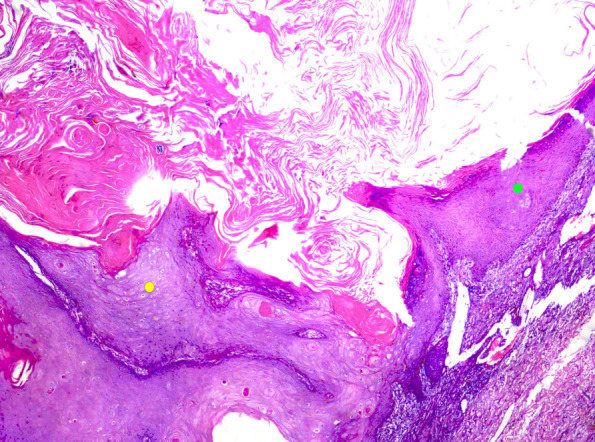

第5版世界卫生组织皮肤肿瘤分类(2022)对命名和诊断进行了修改。以下讨论了重要差异。每一类皮肤肿瘤的变化都有详细的描述,特别强调我们对皮肤不同肿瘤景观的分子发病机制的理解取得了有意义的进展。

The 5th edition WHO Classification of Skin Tumors (2022) has introduced changes to nomenclature and diagnostics. Important differences are discussed below. Changes in each category of skin tumor have been detailed, with particular emphasis on meaningful advances in our understanding of the molecular pathogenesis of the skin's diverse tumor landscape.